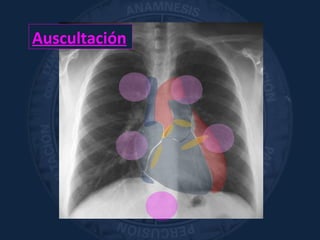

Auscultación

«apreciación con el sentido del

oído de los fenómenos acústicos

que se originan en el organismo»

Laënne

Sist. Circulatorio

Sonidos cardíacos normales, soplos, sonidos agregados.

CARÓTIDAS. Art. RENALES

Pulmón y Vía Aérea

Ventilación alveolar, alteraciones en el flujo aéreo,

sonidos agregados

Abdomen

Ruidos hidroaéreos/Borborigmos